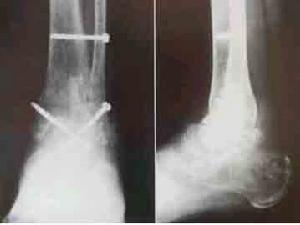

(1)腓骨固定法:採用腓骨下端直切口,遠端向前轉彎。於外踝上6~8cm、處截斷腓骨,將遠段骨的前面脛腓之間切開,保留其外側及後側軟組織,並將此段骨向後翻開,將其內側面鑿成粗糙面,待病灶清除和殘留軟骨面切除後,將脛骨下端和距骨體外側鑿成粗糙面。將後翻的腓骨復位,用3枚螺絲釘固定於脛骨下端和距骨體外側。固定時注意距骨應在內外翻中立位,術後用小腿石膏托固定,拆線後改用行走小腿石膏靴固定3個月。

(2)脛骨片滑動植骨法:經踝前方途徑顯露出踝關節,將足儘量跖屈,顯出整個脛骨下端和距骨體的關節面。病灶清除後,切除殘餘軟骨面,在脛骨下端鑿一長5~6cm、寬2.5cm的骨皮質。在距骨背面相應位置鑿出寬2.5cm、深1.5cm的骨槽。將脛骨片下滑置入距骨的骨槽內,並使脛骨下端與距骨體緊密對合,脛骨片用2枚螺絲釘內固定。術後處理同上。

(3)加壓融合法:取外側或前側途徑手術。清除病灶,切除殘餘的軟骨面,骨粗糙面對合後在脛骨下端和跟骨穿骨圓針 安放關節加壓器,進行加壓融合。

以上三種融合術中,加壓融合法效果好,操作簡單,融合時間短,骨性融合率高。